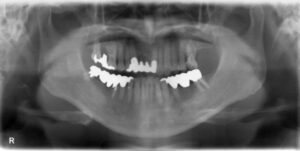

下顎臼歯4本欠損症例

BEFORE AFTER 52歳女性/下4本欠損/インプラント埋込手術 【治療内容】 左下第二小臼歯、第一大臼歯、第二大…